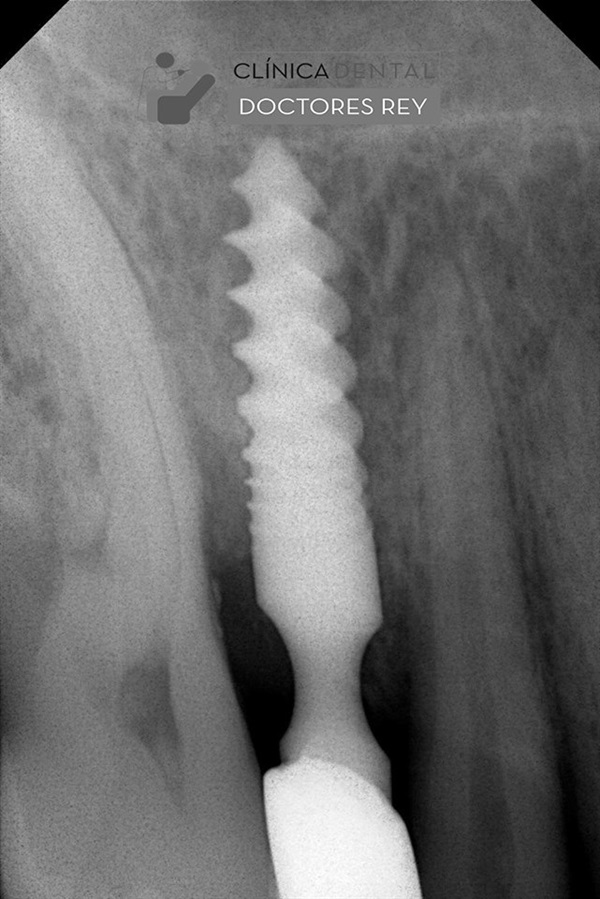

Paciente adulto 66 años, padeció infarto de miocardio, empresario, viaja mucho, conduce mucho tiempo coche, perfeccionista, rigurosamente estricto y preocupado por sus clientes. Consulta por implante dental para zona edéntula en maxilar superior . Le preocupa el espacio edéntulo de un maxilar. Facetas de desgaste, pérdida ósea actual con tratamiento periodontal antiguo, molestias ligeras al masticar, apretador movilidad dental. Discurrir sobre el tratamiento es interesante para dar respuesta a una combinación de hechos asociados derivados de un estado DE PARAFUNCIÓN NEUROMUSCULAR.